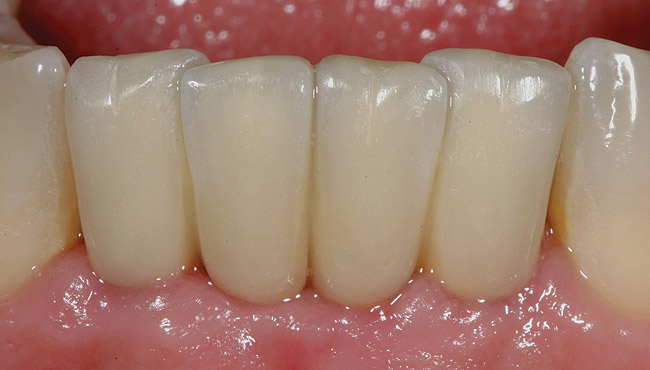

The patient was given postoperative instructions and advised to maintain a soft diet for 6 to 8 weeks to protect the implants. The patient was followed weekly for the first 3 weeks and monthly thereafter. After 4 months of healing, the provisional restoration was removed and the soft tissues were examined. Mature, keratinized gingival tissues were present facially, lingually, and interproximally. Nonkeratinized tissue could be seen at the tissue surfaces of the ovate pontics and in the intrasulcular regions of the implant abutment units. No clinical probing depths beyond 1 mm were found adjacent to the abutments. The healed tissue represented an acceptable clinical result especially in light of the gap that had been present at the time of implant placement (Figure 7A and Figure 7B). Final impressions were made, and the permanent ceramo-metal screw-retained prosthesis was placed within 8 weeks (Figure 8).

This patient has been followed for 4 years with no complications and no discernable clinical changes in soft- or hard-tissue levels.

Figure 8  Final ceramo-metal restoration.

Figure 8